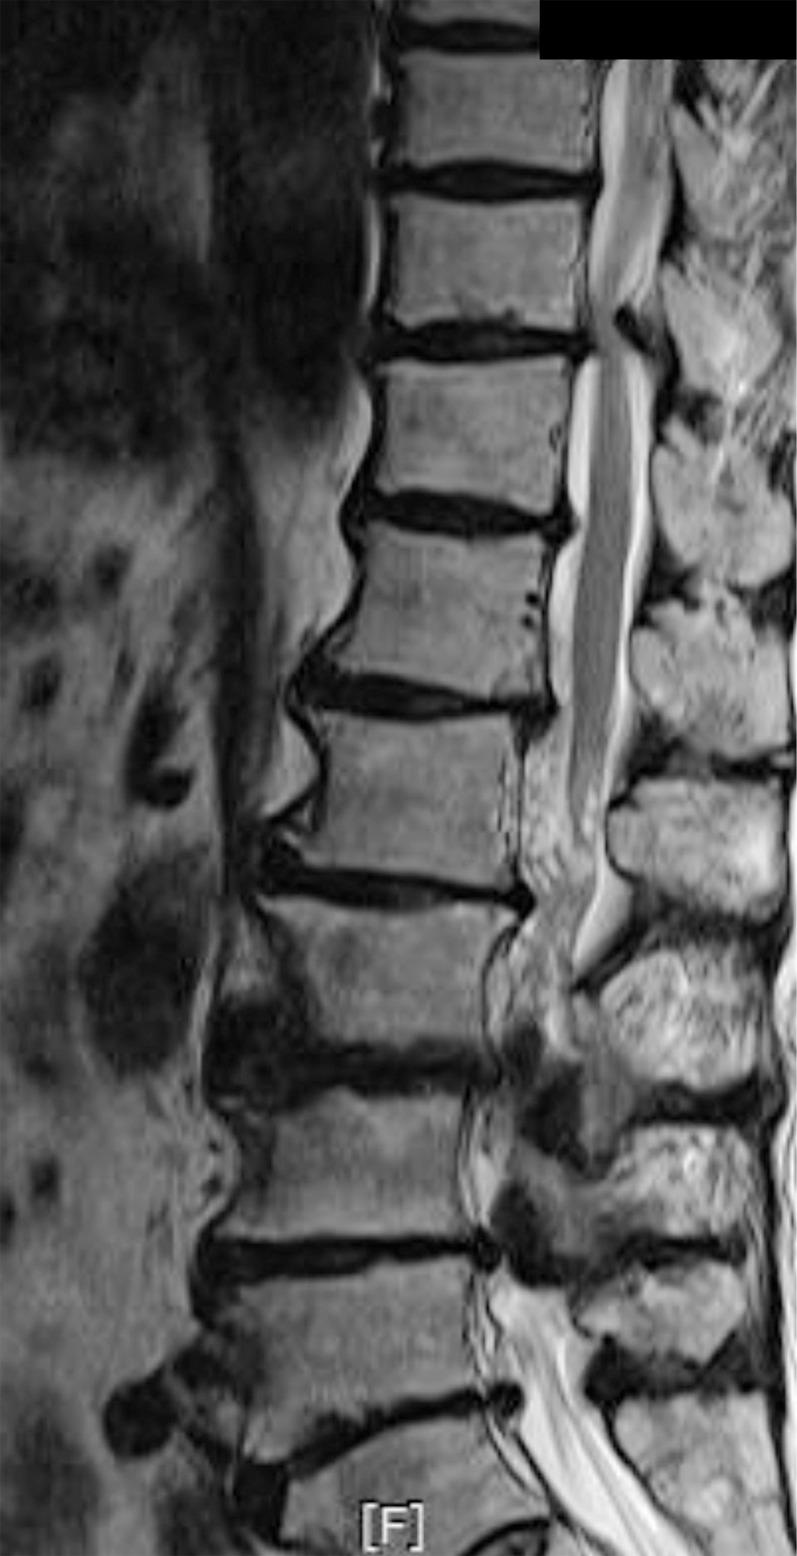

Ossification of the ligamentum flavum is a rare cause of thoracic myelopathy. It develops in East Asians more frequently than in people from other areas. The exact pathophysiology has not been elucidated yet; however, it largely depends on biomechanical alterations, especially changes in the tensile force. Because the spinal cord is compressed from the posterior side, the first and most common clinical manifestation is usually loss of functional gait and spastic paralysis, which develop as the spinal cord compression progresses. The choice of diagnostic imaging is T2 sagittal magnetic resonance imaging scanning. Whole spine scanning is mandatory to identify multiple areas of compression and any associated distal lumbar diseases. Fine computed tomography imaging is necessary to make a differential diagnosis and set up a precise surgical plan. Conservative treatment does not work in this disorder. Decompression surgery is the only option and prognosis after surgical treatment is better with this disorder than with other causes of thoracic myelopathy. The severity of preoperative symptoms and the time interval before surgical treatment are the most important prognostic factors.

黄韧带骨化是胸段脊髓病的罕见病因。东亚地区的发病率高于其他地区。确切的病理生理学尚未阐明;然而,其很大程度上取决于生物力学改变,尤其是张力变化。由于脊髓从后侧受到压迫,最初且最常见的临床表现通常是功能性步态丧失和痉挛性瘫痪,随着脊髓压迫的进展而出现。诊断性影像学检查选择T2矢状面磁共振成像扫描。必须进行全脊柱扫描以识别多个压迫部位以及任何相关的远端腰椎疾病。精细的计算机断层扫描成像对于进行鉴别诊断和制定精确的手术方案是必要的。保守治疗对这种疾病无效。减压手术是唯一的选择,并且与其他胸段脊髓病病因相比,这种疾病手术治疗后的预后更好。术前症状的严重程度和手术治疗前的时间间隔是最重要的预后因素。